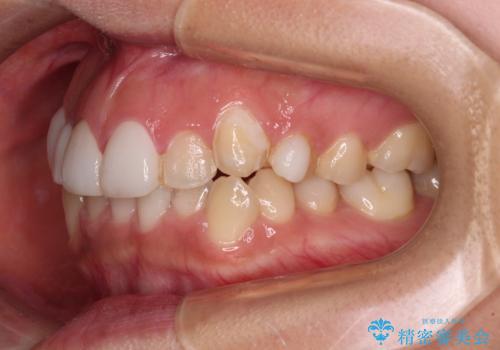

前歯のデコボコが気になる インビザラインによる矯正治療

- 上下前歯のデコボコを気にして来院された患者様です。

インビザラインによる上下歯列の拡大と、IPR(歯と歯の間を削る)にるスペースの獲得により、前歯のデコボコを改善することとしました。